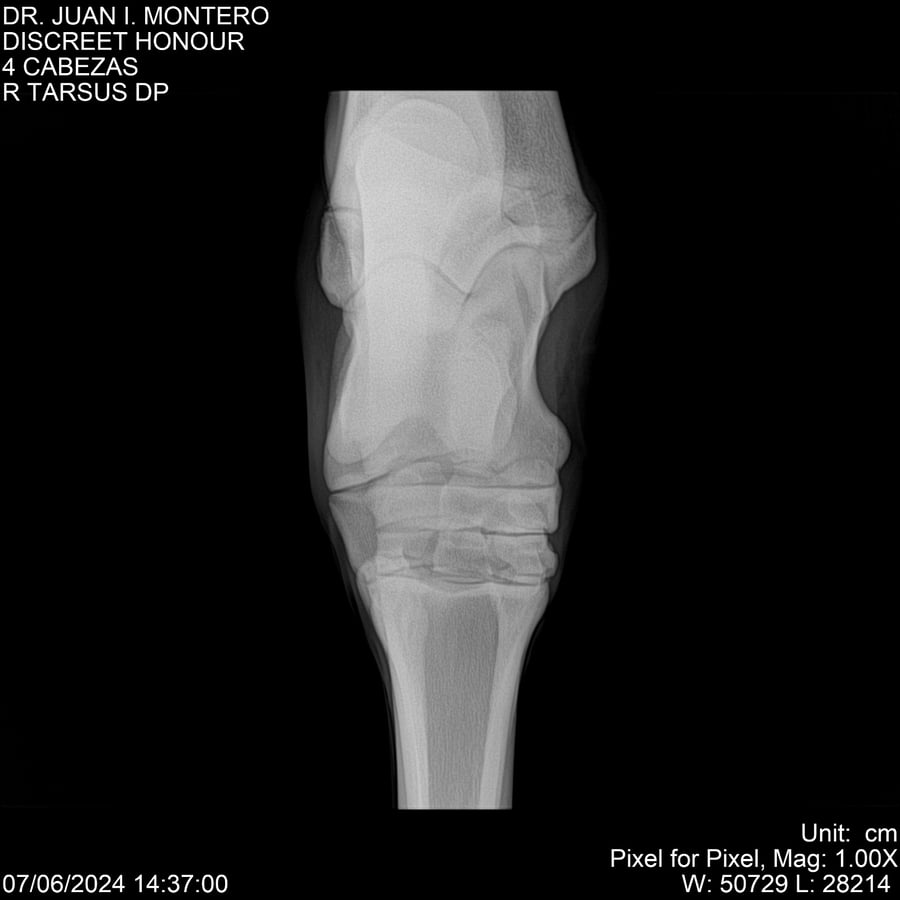

LOTE 6, DISCREET HONOUR 🔥 🔥 🔥 Lote Anterior Volver al remate Lote Siguiente Ficha Contacto Montevideo - Ficha del Lote Identificador: #281093 Categoría: Yeguarizos Montevideo - 82 Visualizaciones ClicData Contacto Empresa: Abelenda N. R., Walter Hugo Nombre*: Teléfono* : E-mail* : Mensaje Enviar Registrese gratis Este contenido Exclusivo está disponible sólo para usuarios registrados Ingresar